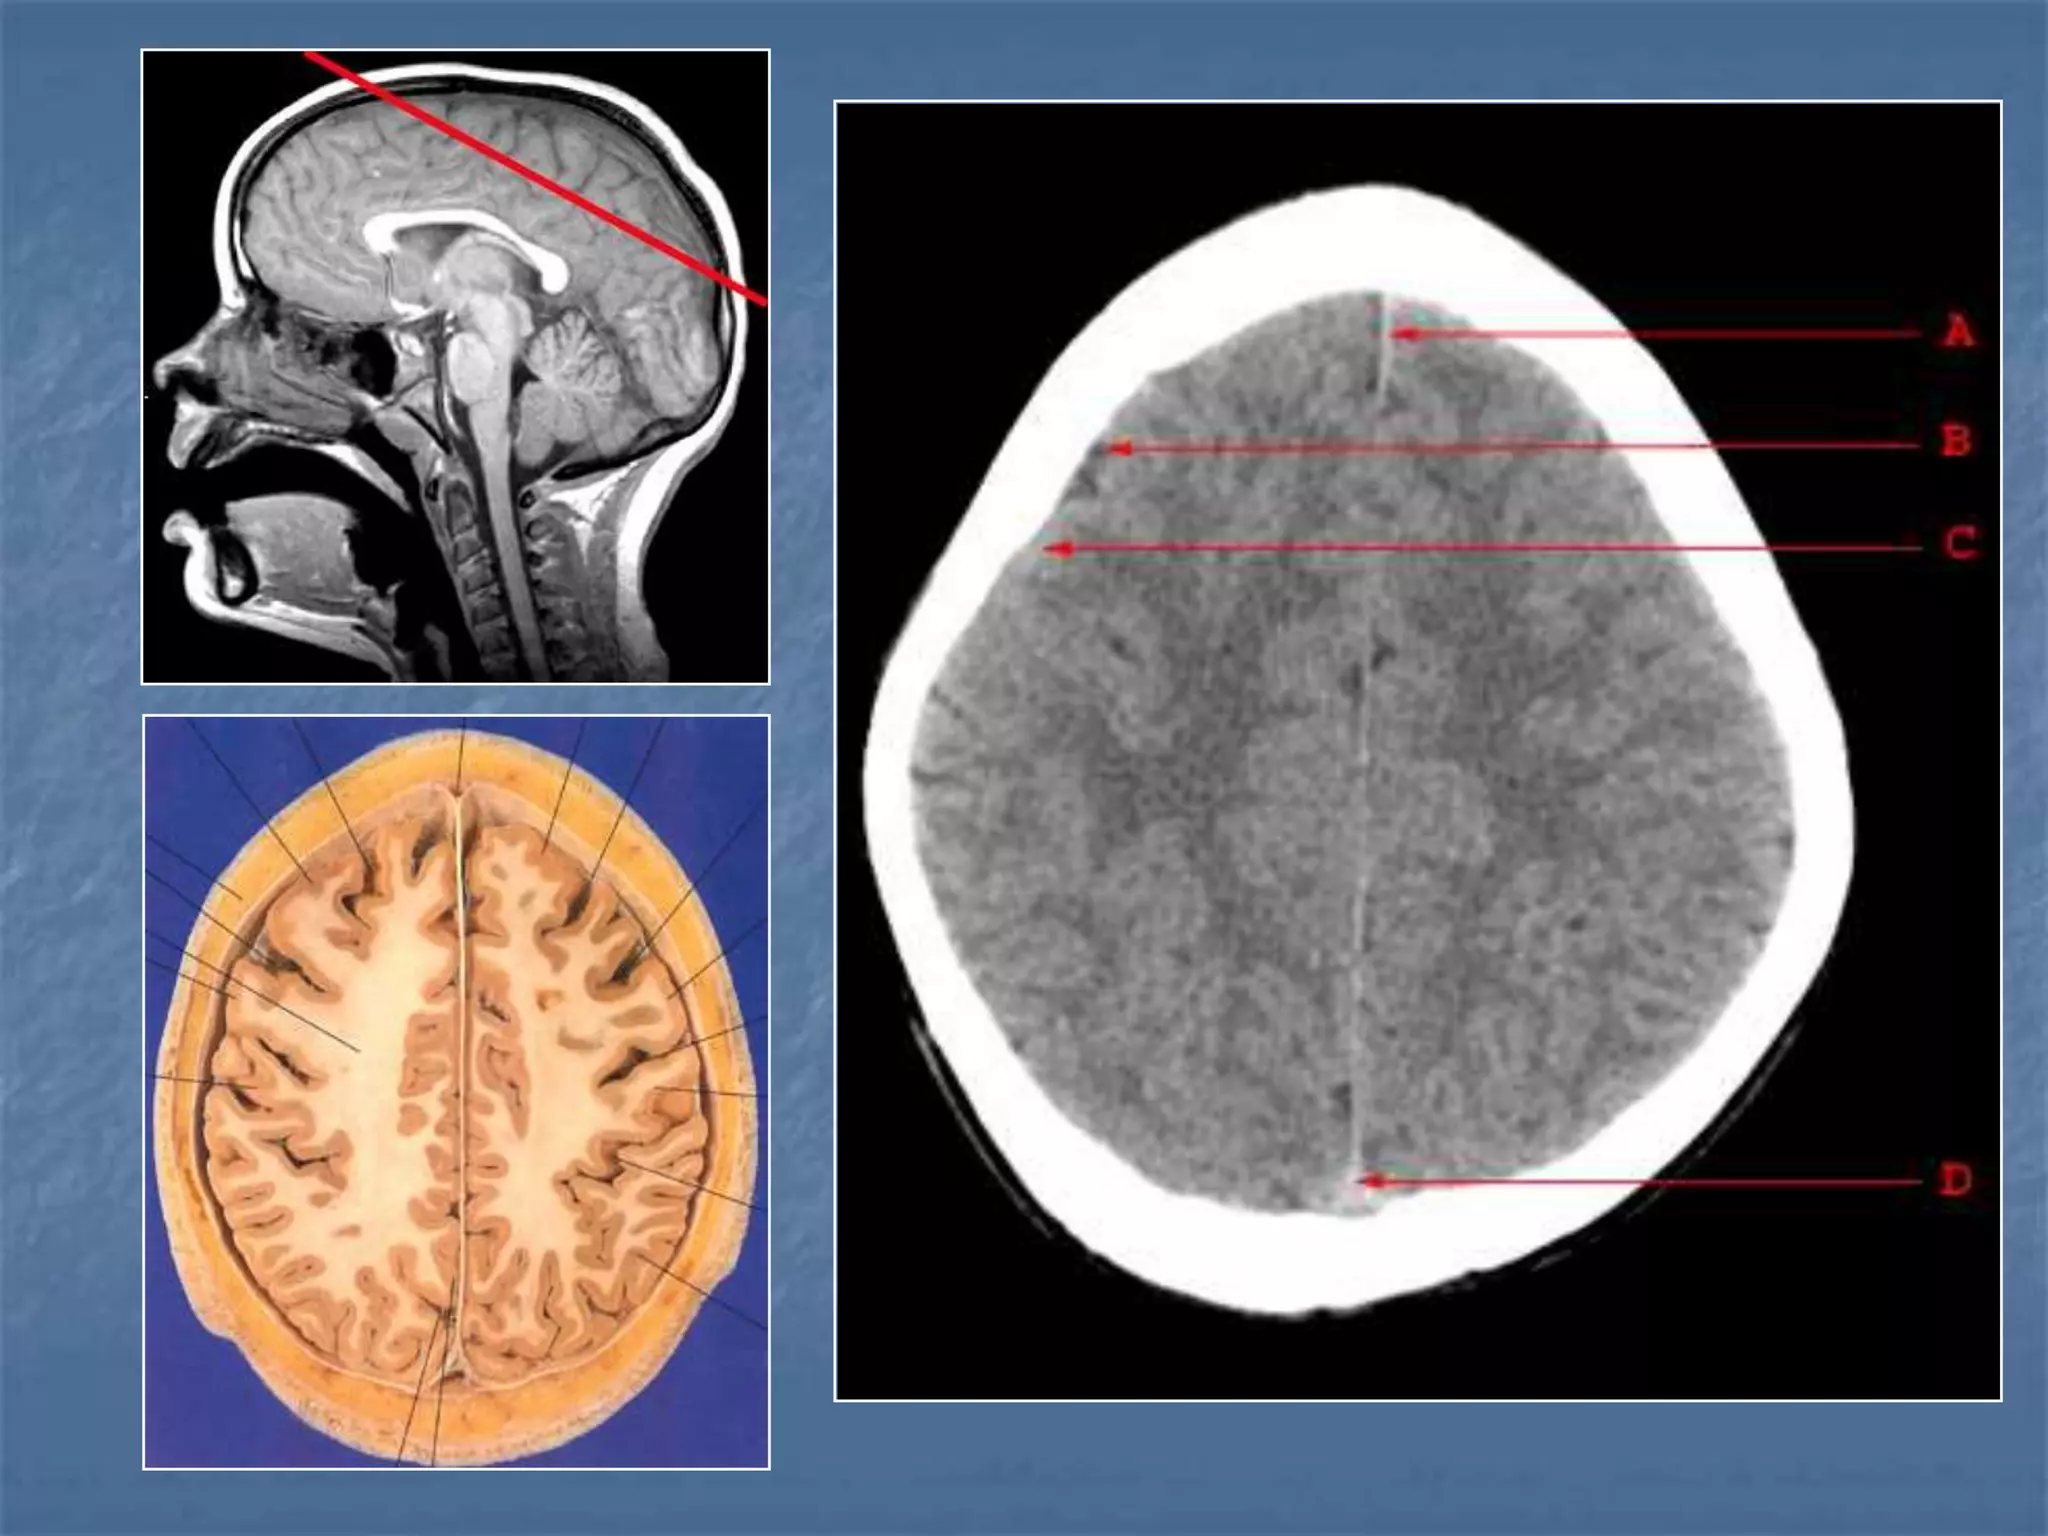

Plain CT Contrast CT

Brain Window Bone Window

Descriptive Terms …….

 Hypodense / Hypointense

 Isodense / Isointense

 Hyperdense / Hyperintense

Hounsfield Units

AIR - - 1000

FAT - - 30 to -100

CSF - 0

GREY MATTER - 32 - 41

WHITE MATTER - 23 - 34

ACUTE BLOOD - 56 - 76

CALCIFICATION - 60 - 400

BONE - 1000